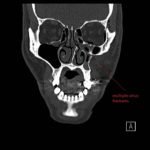

Physical exam showed marked left palpebral subcutaneous crepitus, as well as bulbar and palpebral conjunctival bulging. Visual acuity was normal with intact extraocular movements, and normal pupillary exam. Computed tomography (CT) imaging of the face was obtained and revealed multiple displaced fractures involving the left orbital floor and zygomatic arch associated with moderate periorbital and postseptal extraconal gas, resulting in orbital proptosis.